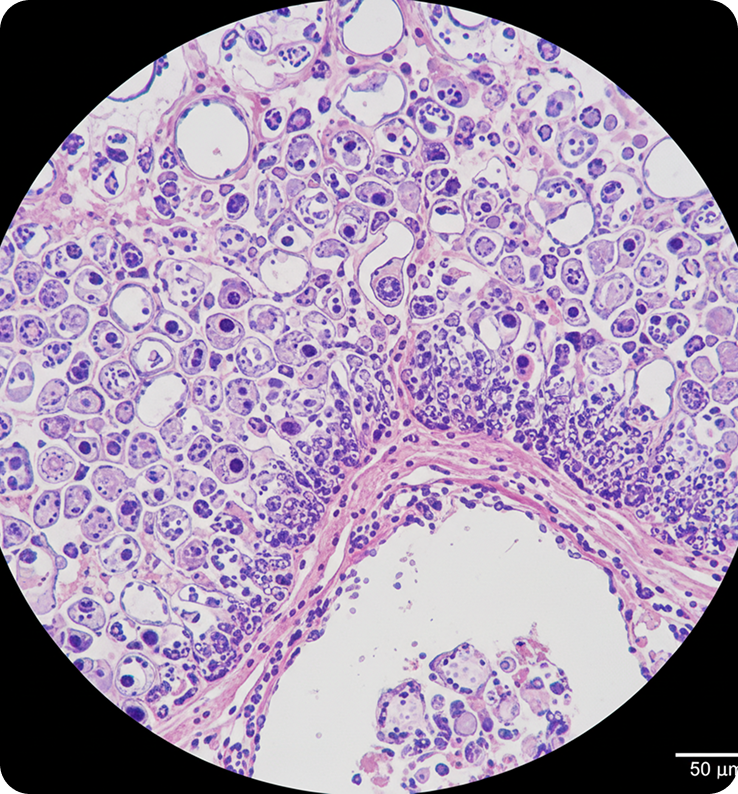

Neoplasias de Ovário

Diferentemente das NICs, que podem ser detectadas através do rastreio rotineiro, as neoplasias de ovário costumam ser silenciosas em estágios iniciais, tornando o diagnóstico mais desafiador.

Diagnóstico

Assim como explicado na página de NIC, a confirmação depende da avaliação histopatológica:

Confirma o tipo de lesão, grau e extensão.